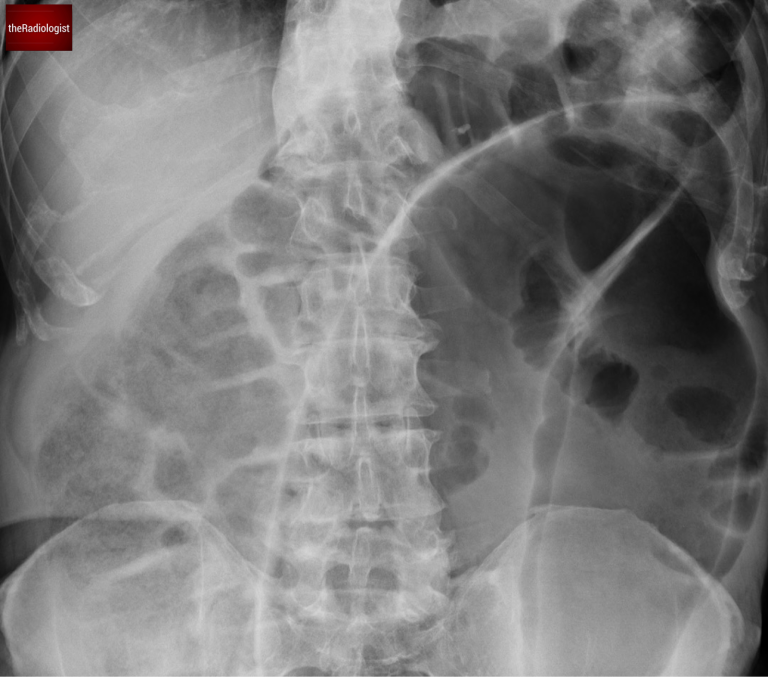

We can see there is a single massively dilated bowel loop – when you see this you need to consider volvulus.

What is volvulus? Volvulus refers to a twisting of the bowel around its mesentery, resulting in obstruction. This condition often occurs in parts of the bowel that are less fixed. Within the colon, the two most common sites for volvulus are the caecum and the sigmoid colon.

Let’s revisit the first X-ray. The single, dilated bowel loop has a coffee bean appearance—a classic but not entirely specific sign of sigmoid volvulus. The absence of haustra within this loop further supports the diagnosis of sigmoid volvulus.

The massively dilated bowel loop has the appearance of a coffee bean.